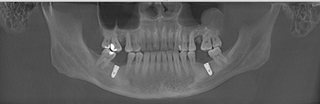

麦芽口腔中方院长对王先生的口腔ct片进行专业深度的分析之后,决定为其种植麦芽数字化生物种植牙,“麦芽数字化生物种植牙”,运用数字化、纳米、微痛、保证口腔功能重建和舒适修复的同时,兼顾口腔美学修复,既能快速修复牙齿,恢复咀嚼,同时能够达到较好的美观程度,术中采用STA美国微痛麻醉,确保了手术全程的舒适度,且采用数字化3D种植导板技术,能够更加准确、更加快速找到最佳植入位置,有效避免手术过程遭受痛苦,保证了手术成功率。